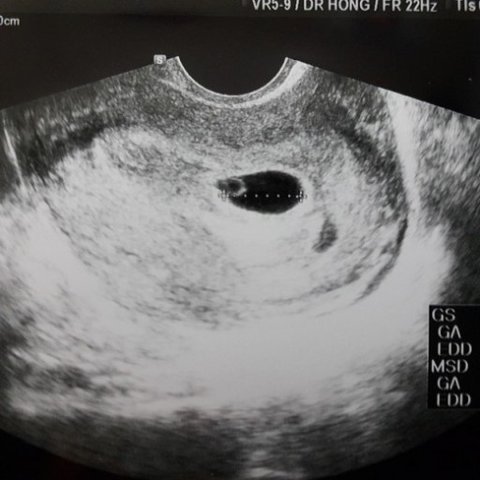

위에 초음파사진은 그 당시에 보여줬던 사진입니다

초음파로 태낭? 같은것도 봤다고